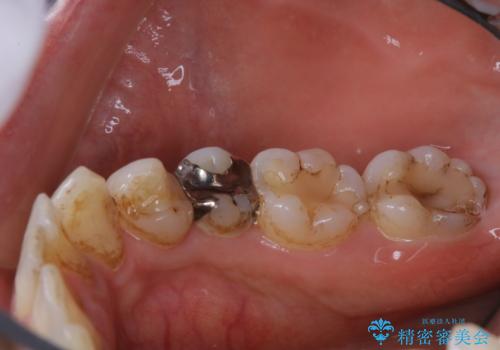

歯の表面に、茶色く色が残っている所がありますが、これは詰め物の変色によるものです。以前に、CR(コンポジットレジン)による虫歯治療がされています。

CRは経年的劣化や、着色してしまうことがあります。PMTCでクリーニングを行うと、古いCRが目立つことがあるため、気になる際は詰め替えを行います。

茶色くなっている部分が、着色なのか、劣化なのか、虫歯によるものなのかは判別が難しいことがあります。そのため、定期的にPMTCを行うことで状態の確認が的確に行えます。